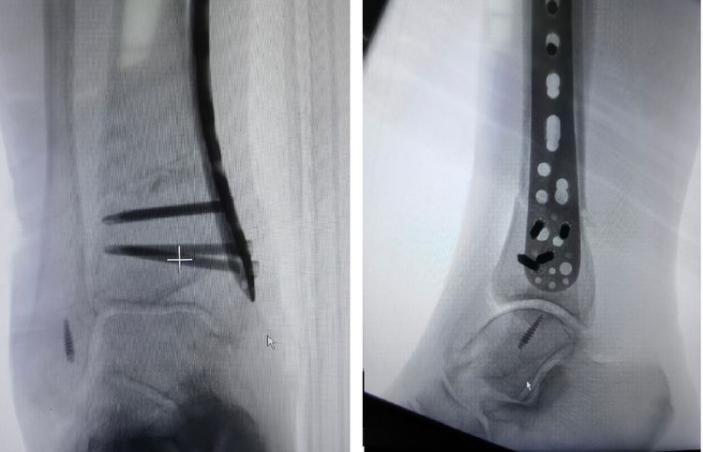

科主任杜虎羽認真分析術前X線片、CT及MRI檢查結果,并根據高大娘的具體情況制定了周密的治療方案。7月30日,科室專家團隊在腰麻下為高大娘實施了“左踝關節鏡下探查+關節腔清理術;右踝關節周圍韌帶松解+骨贅清除+踝上截骨術+取自體髂骨植骨術。”

分別于右踝內側、外側清理大量增生骨贅,這些增生的骨贅,見證了大娘多年的疼痛心酸史。

右踝上截骨及外側韌帶修復,術中關節間隙匹配。